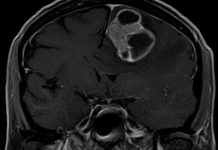

Rakovina plic v mnoha případech metastazuje do mozku

Nemalobuněčný karcinom plic tvoří 85 % případů rakoviny plic. U 40 % pacientů se pak vyskytuje v pokročilém stádiu. To v praxi značí metastáze do dalších orgánů, často pak do mozku.